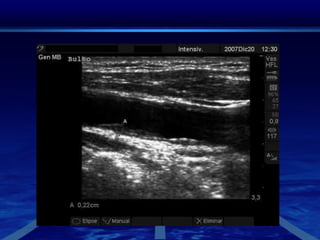

Ultrasonido CarotideoEl ultrasonido Doppler es el método de imagen más utilizado en el estudio de las carótidas Ofrece una evaluación no invasiva para detectar las placas de ateroma como causa de tromboembolismocerebral.Permite definir sus características y el grado de estenosis que producen, muchas  veces constituye el único estudio antes de la cirugía o la colocación de stent.

En el estudio de las carótidas, se estudian las arterias carótidas, los grandes vasos del cuello que llevan la sangre al cerebro. La ecografía carotidea puede mostrar placas que estrechen la arteria y reduzcan el flujo de sangre que llega al cerebro.la ecografía no conlleva exposición a radiación ionizante, lo que significa que puede repetirse la exploración sin preocupación por la acumulación de radiación. Además, ultrasonidos de carótida es una técnica en tiempo real que nos indica como está el flujo sanguíneo en el momento de realizarse la exploración.

Ultrasonido CarotideoEl ultrasonidoDoppler es el método de imagen más utilizado en el estudio de las carótidas Ofrece una evaluación no invasiva para detectar las placas de ateroma como causa de tromboembolismocerebral.Permite definir sus características y el grado de estenosis que producen, muchas  veces constituye el único estudio antes de la cirugía o la colocación de stent.

En el estudiode las carótidas, se estudian las arterias carótidas, los grandes vasos del cuello que llevan la sangre al cerebro. La ecografía carotidea puede mostrar placas que estrechen la arteria y reduzcan el flujo de sangre que llega al cerebro.la ecografía no conlleva exposición a radiación ionizante, lo que significa que puede repetirse la exploración sin preocupación por la acumulación de radiación. Además, ultrasonidos de carótida es una técnica en tiempo real que nos indica como está el flujo sanguíneo en el momento de realizarse la exploración.